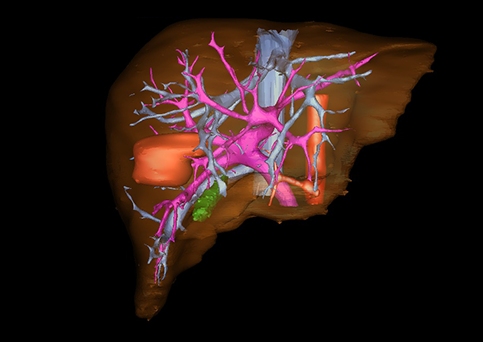

近年来由于数字医学的发展,基于可视化三维重建技术的计算机辅助手术系统极大推进了小儿肝脏肿瘤的精准手术的进步。可以立体透视肝脏解剖、精确掌握肝段的边界、精确测算肝段乃至任意血管所支配的功能体积、准确定位病灶及其与邻近血管的解剖关系,最终对不同手术方案进行比较、筛选和优化。因此,计算机辅助手术规划系统是实现精准肝切除的有力辅助工具,是未来数字外科、精准外科等21世纪外科新理念的重要技术支撑。

计算机辅助手术规划系统具有良好的操作可行性、计算准确性和三维显示效果,可半透明、交互式显示真实的肝内立体解剖关系和空间管道变异,准确计算肝内管道的直径、走行角度,两点间的垂直距离,和任意血管的支配或引流范围等传统二维影像无法获取的信息,有助于实施个体化手术,提高了手术的确定性、预见性和可控性。计算机辅助手术规划系统可直观显示预留肝脏的结构和功能,并可通过虚拟切割功能辅助术者对手术方案进行蹄选和优化,系统评估手术风险和制定对策,改变了部分二维规划的术式和切除范围,使部分二维规划认为不能切除的患者成功手术,提高了手术的根治性、安全性和病变的可切除性,更加符合精准肝脏外科的术前规划要求。详见第11章。

随着计算机技术及影像检查技术的不断发展,以精确的术前影像学和功能评估、精细的手术操作为核心的精准肝切除技术日益受到重视。基于数字医学的计算机辅助手术技术(computer-assisted surgery,CAS)则是实现肝脏精准手术操作的基础。计算机辅助手术系统(CAS)可将术前二维(two dimensional,2D)的CT/MRI影像数据进行三维(three dimensional,3D)重建,建立个体化的肝脏三维解剖模型,清晰显示肝脏内脉管系统的走行及解剖关系,还原病灶与其周围脉管结构的立体解剖构象,准确地对病变进行定位、定性和评估,制定合理、定量的手术方案,实施个体化的肝脏血管取舍分配方案及实施精准肝脏手术。一般认为CAS包括:创建虚拟的患者的图像;患者图像的分析与深度处理;诊断、手术前规划、手术步骤的模拟;术中实时导航。应用本技术后,由于可以更清晰地看出肿瘤的界限,特别是根据肝血管的显影,判断出肿瘤与门静脉及肝静脉的关系以在手术前较准确地估计出手术成功切除的可行性。以往部分根据普通强化CT判断无法手术的病例而被评估为可以成功切除并手术成功。

图23:肝中叶肿瘤二维CT图像